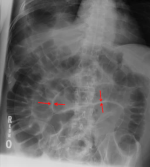

| B | • Bowel gas | • 3,6,9 rule - small bowel <3cm, large bowel <6cm, caecum and sigmoid <9cm |

| B | • Bones | • ribs, lumbar vertebrae, sacrum, coccyx, pelvis and proximal femurs |

| C | • Calcification • artifacts | • arterial Ca++, phelobliths, calculi • clips, tubes, implants |